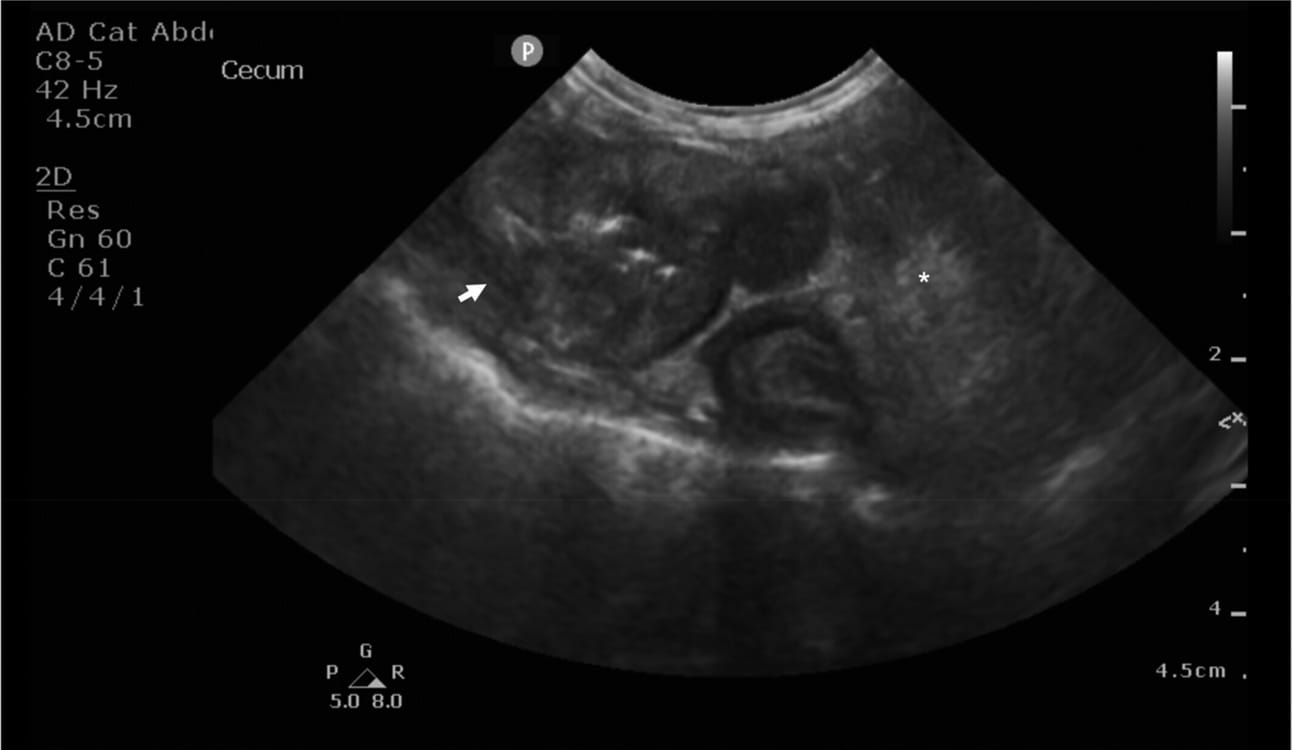

Ultrasonographic image of a mass at the level of the ileocolic junction (white arrow). The mass shows loss of layering, circumferential thickening and eccentric growth. The wall is heterogeneously mixed in echogenicity because of hyperechoic areas. The surrounding peritoneum is hyperechoic (asterisk).